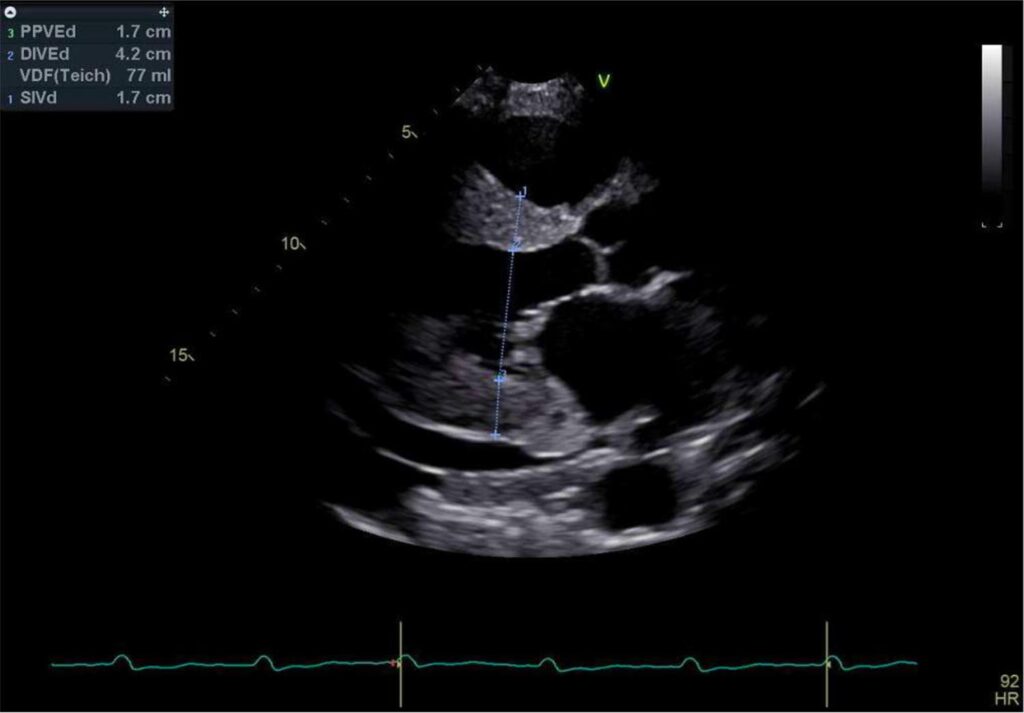

A amiloidose sistêmica é um grupo de doenças causadas pela deposição de uma proteína amiloide que forma fibrilas e deposita nos tecidos. Pacientes com mutação de transtirretina (TTR) Val122Ile têm idade e um fenótipo semelhante àqueles com amiloidose cardíaca do tipo selvagem, causando uma cardiomiopatia restritiva de início tardio com neuropatia mínima em uma idade média de início de 69 anos. A mutação homozigótica é rara. Relatamos um paciente do sexo masculino que apresentava insuficiência cardíaca de início recente e fenótipo de cardiomiopatia hipertrófica. A cintilografia com tecnécio evidenciou captação cardíaca e ausência de imunoglobulinas circulantes, sugerindo amiloidose cardíaca TTR. A análise genética confirmou a amiloidose cardíaca causada pela proteína TTR mutante homozigótica Val122Ile.